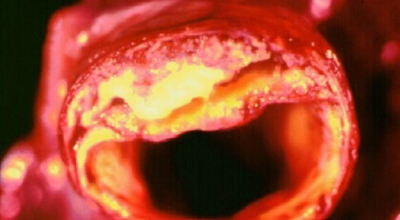

호두, 아몬드등의 견과류 섭취는 필수지방산이 많이 포함되어있다고 하며 콜레스테롤을 낮춰주어 고혈압 감소시키는 음식입니다. 등푸른 생선에 많이 들어있는 불포화 지방산은 혈관벽에 붙어서 혈관을 좁게 하는 포화지방을 없애주는 효과가 있어 고혈압에 좋으니 필수로 챙겨드시기 바래요.